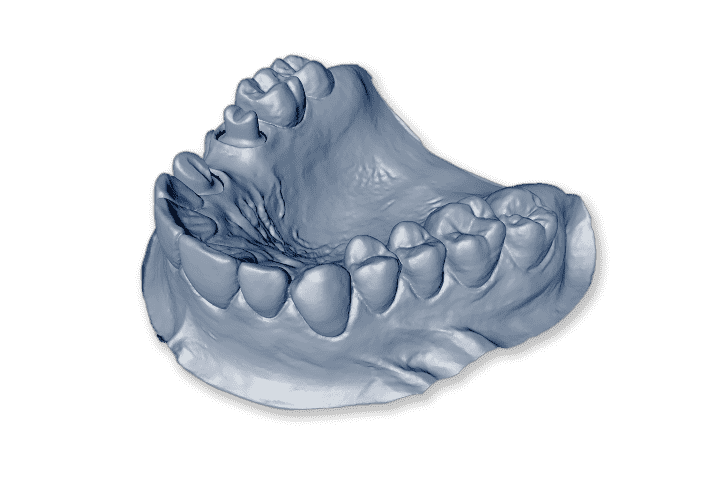

NTI splint is a small, transparent dental device made from plastic, created to be placed over the front teeth during the night. When the time comes to remove it, NTI dental splint should be run in the warm water. It is classified as a partial occlusal splint.

At Pindan Dental Laboratory, we custom-create an NTI splint to fit your patient’s bite perfectly. The design also features a snap-in fit that ensures the NTI dental splint remains securely fitted through the night. The device serves to reduce clenching and negative impulses transmitted by nerves. For some patients, NTI splint shows immediate results, while others will notice the benefits after a couple of uses.

Owing to our years of experience, we understand just how important it is to fabricate a dental device that fits the patient’s mouth ideally. Especially for patients who are expected to wear the guard for a prolonged period, unfitting dental devices may cause great discomfort and a range of other dental issues.

To avoid any negative side effects, we establish a strong relationship and seamless communication with a dental practice in an effort to create the most optimal NTI dental splint for the patient’s specific case. We will take you through the necessary process to establish the shape that will fit the patient perfectly and help treat bruxism or temporomandibular disorder.